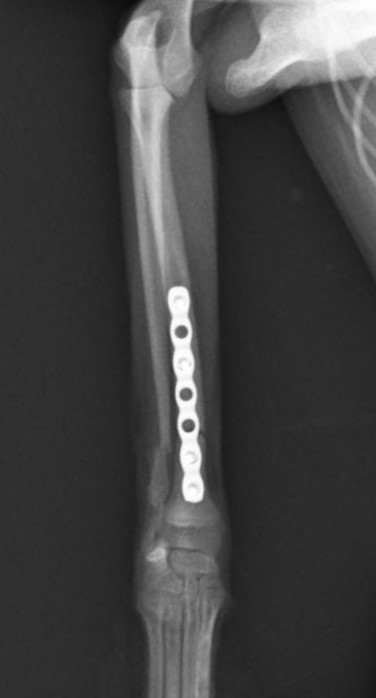

右前腕骨折のポメラニアンちゃんが来院されました。橈尺骨骨折は動物病院では一番よくある骨折です。ロッキングプレートであるTAITAN1.2で対応しました。治りも順調で元気に帰りました。よかったね。